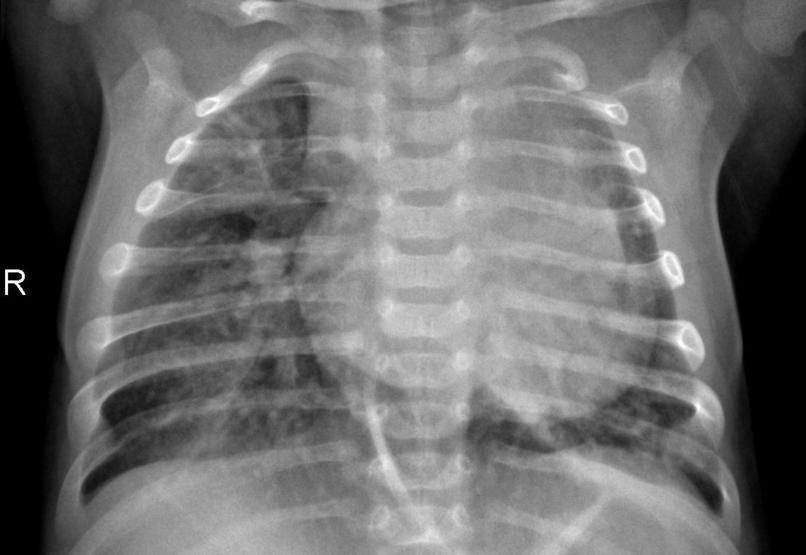

The AI Clinic webpage accepts medical images (such as xray, mri, photos) and outputs the diagnosis from those images. (Diagnosis include: Brain Cancer, Alzheimer's, Monkey Pox, Pneumonia). This is achieved through trained machine learning models. The webpage also automatically outputs the most cited Google Scholar research papers related to the specific diagnosis. And although, it is primarily intended for the use of medical professionals (doctors, nurses, technicians, etc) the general public can reap its benefits too.

Machine Learning Models: We have trained 4 machine learning models (for now!) - Brain Cancer, Alzheimer's, Monkey Pox, Pneumonia - from datasets obtained from reliable sources in Kaggle. To further increase accuracy, we also applied data augmentation to our datasets and used transfer learning techniques. Flask Framework: We created our webpage - frontend and backend - using the flask framework. JavaScripts and CSS added functionality and UI/UX components respectively. Microsoft Azure: We set up an Ubuntu Server on Microsoft Azure from scratch. We hosted our full-stack environment on the ubuntu server primarily to make it more production-friendly for us and for scalability in the future.